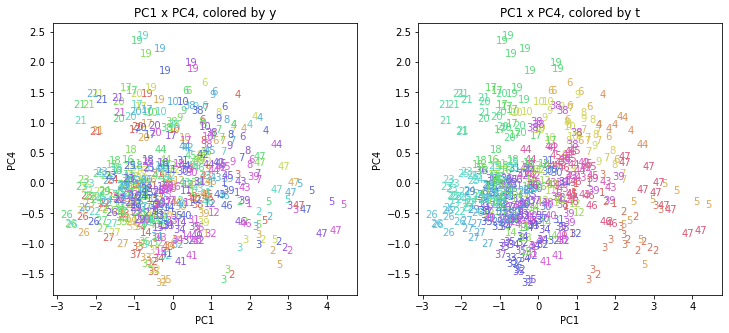

PCAの結果の第n主成分をPCnと表記します。

医療費データの場合と同様に、PCAの結果を見やすく表示するため、seabornのカラーパレットを使って、年月別、都道府県別に色分けして図示してみます(左側が年月別に色分け、右側が都道府県別に色分け)。PC1~PC8まで表示しました。

都道府県番号の表示

上の色分けだけでは都道府県が区別しにくいので、医療費データの場合と同様に、点の代わりに都道府県番号をプロットした図も描いておきます(色分けは上と同じ)。

医療費データの場合ほどはっきりとはしていませんが、PC2が概ね時間の経過を表す成分で、残りの成分が時点によって変わらない地域の特徴を表す成分となっているようです。

また、PC1×PC3を見ると、47沖縄が他の都道府県からかなり離れたところに位置しており、沖縄の地域差が際立っているのが分かります。これは、以前別の記事で年齢階級のない健診データでPCAを実行した場合と似た結果となっています。